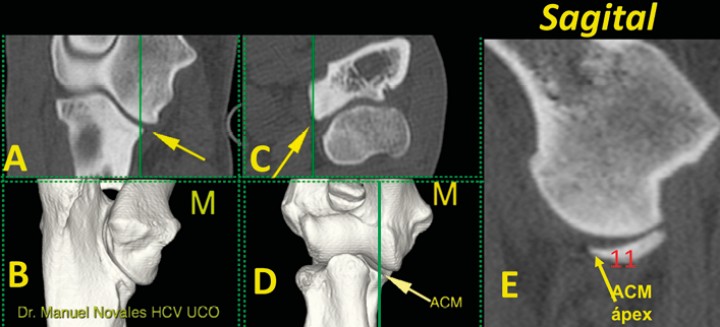

<p>Imagen tridimensional en visión caudomedial (<strong>A</strong>), craneal (<strong>B</strong>), así como en los planos dorsal (<strong>C</strong>), sagital (<strong>D</strong>) y transversales (<strong>E</strong>) a nivel de la ACM (flecha) señalado en las líneas verdes (C y D). En estos planos valoramos el ápex (1) y la incisura radial (2) (M: lado medial).</p>

Figura 5

Imagen tridimensional en visión caudomedial (A), craneal (B), así como en los planos dorsal (C), sagital (D) y transversales (E) a nivel de la ACM (flecha) señalado en las líneas verdes (C y D). En estos planos valoramos el ápex (1) y la incisura radial (2) (M: lado medial).

En el plano transversal nos fijamos sobre todo en la ACM, especialmente a dos niveles: a) a nivel del ápex que reconocemos por aparecer solamente dos huesos (el cúbito y el radio); b) proximalmente al ápex (donde aparecen los tres huesos, incluido el húmero). En este plano transverso es importante valorar: 1) la morfología del ápex (redondeada o puntiaguda, pero sin fragmentaciones, fisuras, cambios de densidad u osteofitos); 2) la escotadura (incisura) radial que tiene que mostrar una curvatura regular, sin alteraciones en su contorno y bien adaptada al radio; 3) la ausencia de reacciones óseas (esclerosis u osteofitos) en ninguno de los huesos implicados (Figs. 5 y 6) (Vídeo 2).